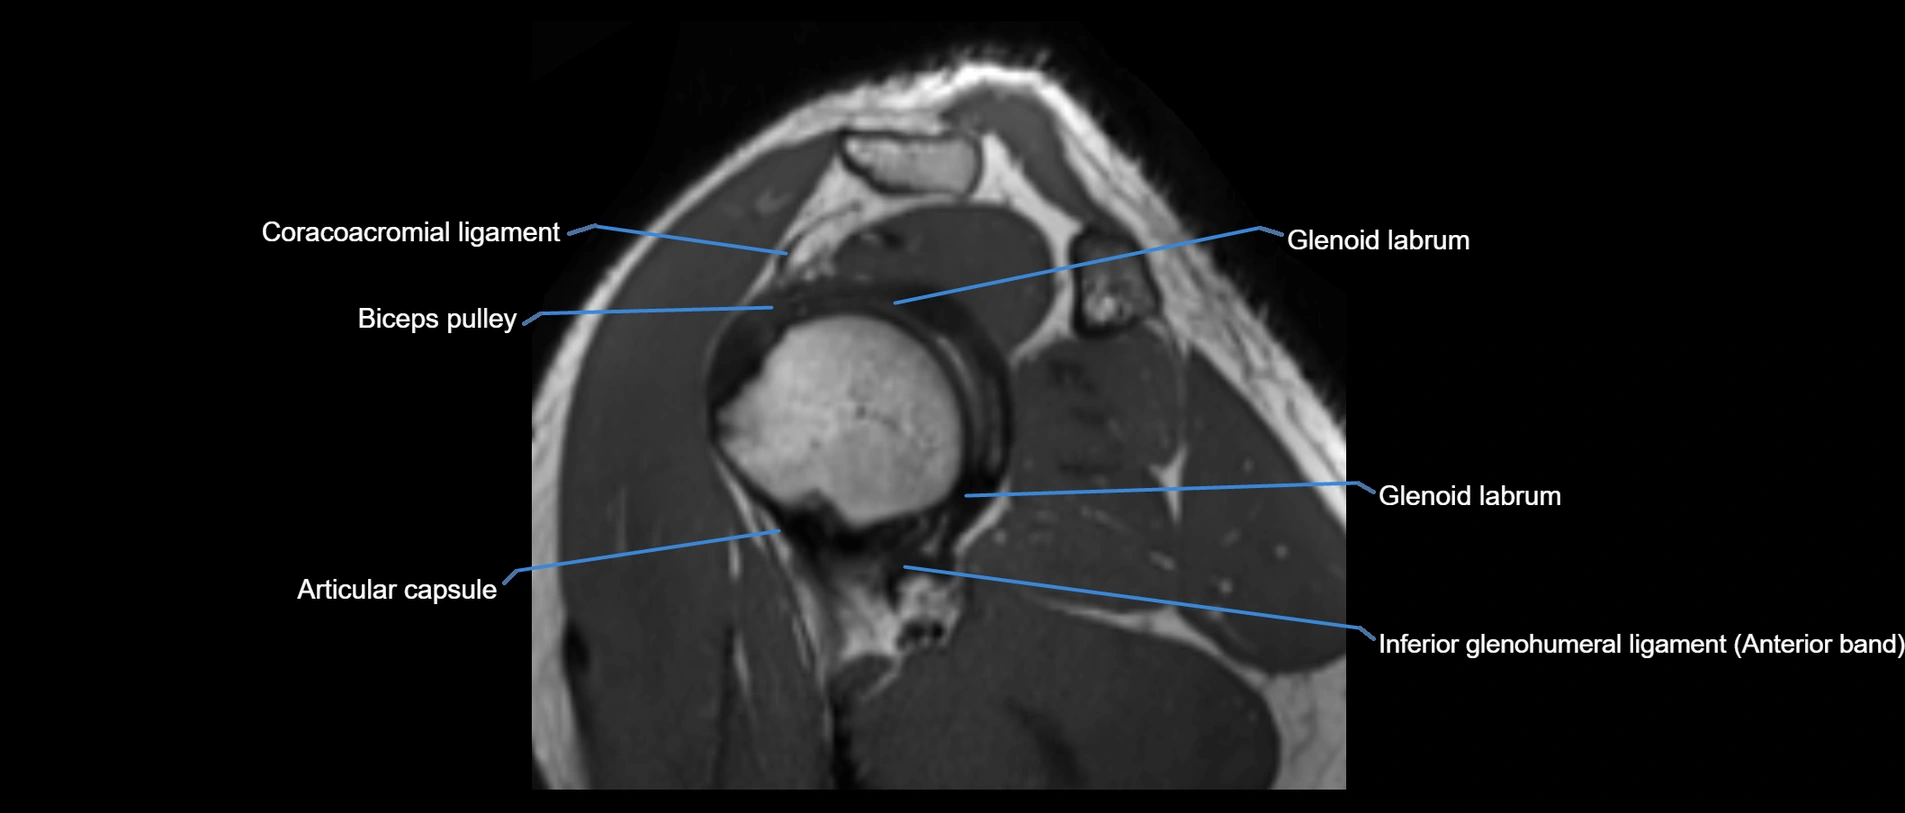

MRI Appearance

• T1-weighted images:

• Normal ligament: Low signal (dark linear band) spanning acromion to clavicle.

• Surrounding fat planes: Bright, delineating the ligament clearly.

• Marrow of clavicle and acromion: Bright due to fatty content.

• Tears: Discontinuity or irregular thickening with intermediate-to-bright signal.

• Chronic injury: Thinning, fraying, or irregular low-signal fibers with adjacent scarring.

• T2-weighted images:

• Normal ligament: Low signal, homogeneous.

• Partial tear or sprain: Focal hyperintensity or thickening.

• Complete tear: Discontinuity with fluid-bright gap between clavicle and acromion.

• Associated edema: Bright signal in distal clavicle or acromion marrow.

MRI images

image